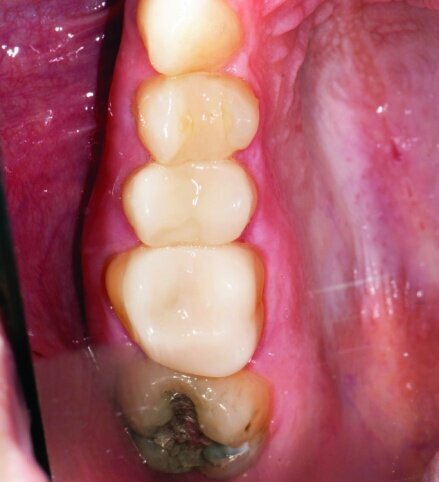

The restorations were then polished (Fig. 34). For #3 e.max restoration, the burs were NTI Cera Glaze—green, blue and yellow, in order. The green prepolisher was not used on the Empress restoration for #4.

The final result was minimally invasive restorations that appear and function naturally, while decreasing risk of tooth fracture, and minimize further risk to the teeth. (Figs. 35a–36b).